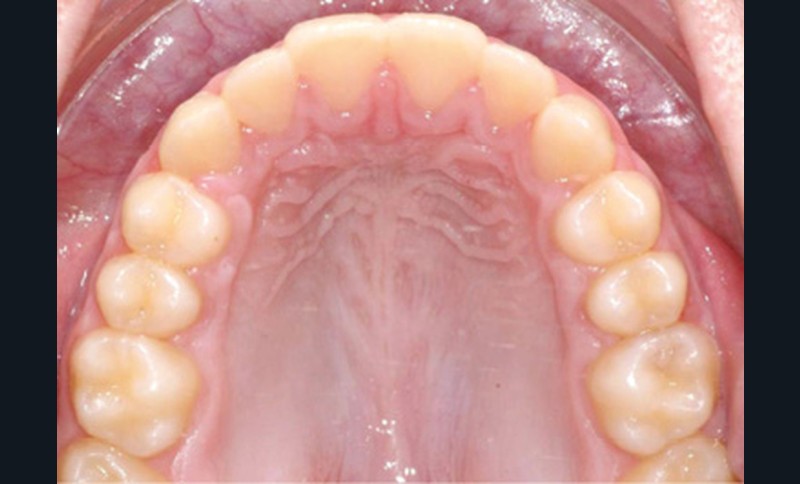

Quelques années plus tard, au moment de démarrer sa prise en charge orthodontique, la patiente présentait à nouveau une béance antérieure, un décalage des milieux incisifs de 2 mm et le problème transversal avait récidivé. Lors de l’examen clinique, elle présentait un inversé d’occlusion bilatéral postérieur et une ventilation buccale exclusive. À la suite du refus de réaliser l’amygdalectomie de façon précoce, elle ronflait toujours et sa déglutition ne s’était pas modifiée malgré des séances d’orthophonie (fig. 7 à 15).